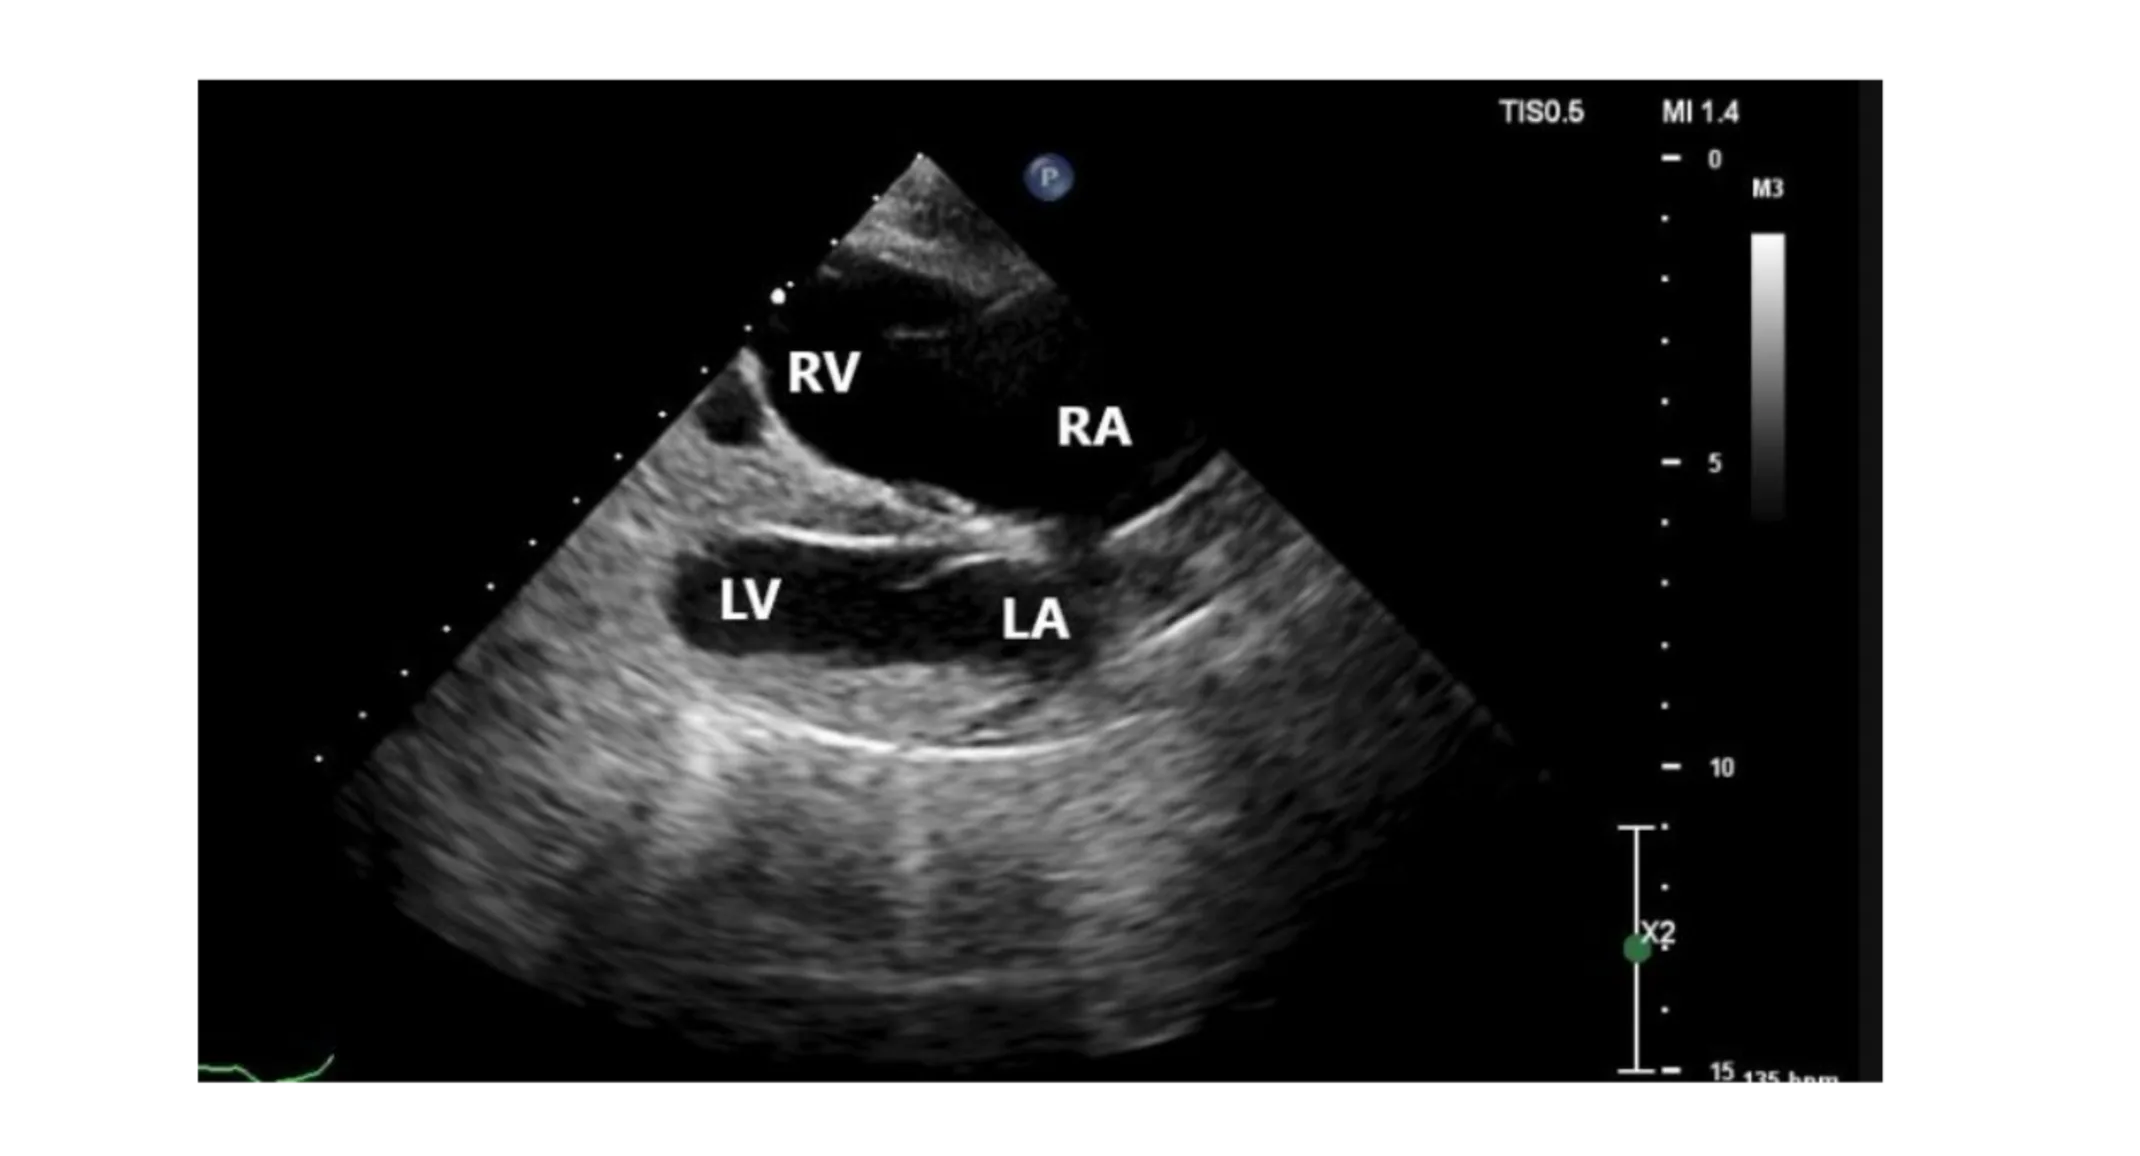

Echocardiogram via consultation with Cardiology Service

Normal left-sided chamber dimensions

Moderate right atrial enlargement

Marked right ventricular enlargement

Slightly thickened mitral valve with mild mitral regurgitation

Mildly thickened tricuspid valve with severe tricuspid regurgitation

Regurgitation velocity 2.39 m/s (pressure gradient 23 mmHg, estimating normal systolic pulmonary arterial pressure)

Mild pulmonary insufficiency (end-diastolic velocity 1.57 m/s [pressure gradient 10 mmHg, estimating normal diastolic pulmonary arterial pressure])

ECG during echocardiogram indicated sinus rhythm with occasional VPCs in isolation

RA=right atrium; RV=right ventricle; LA= left atrium; LV=left ventricle